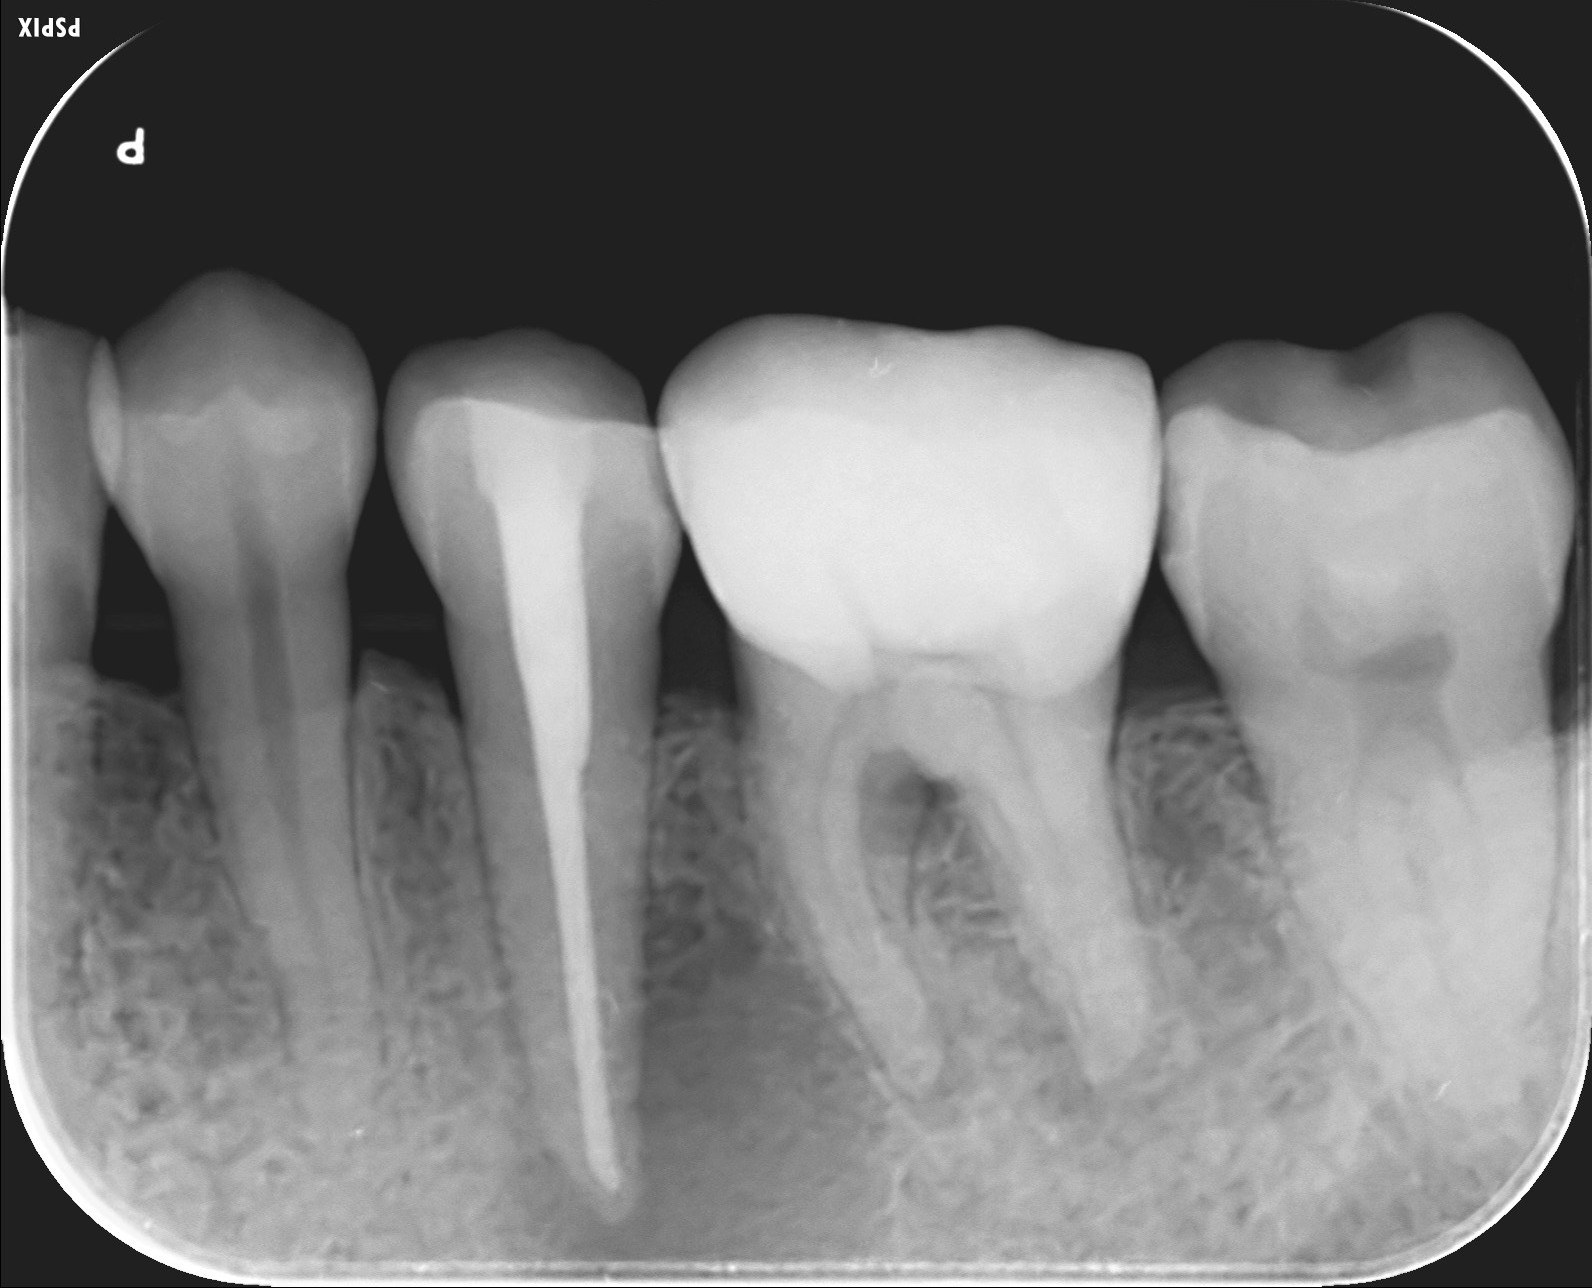

歯根嚢胞

左下5番の歯根を黒く取り囲む根尖病変が認められます。 -

1年6ヶ月後;治癒

根尖病変は消退傾向になります。 -